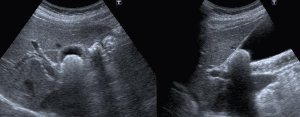

腹部エコー検査

腹部には肝臓・胆嚢・膵臓・腎臓など様々な臓器があります。エコー検査ではそれぞれの臓器の腫瘍の有無や形態の異常や炎症の状態などがわかります。また、当院では造影エコー検査で腫瘍の性質や肝細胞がんの診断や治療効果判定なども行っております。

【肝 臓】 -

【胆 嚢】